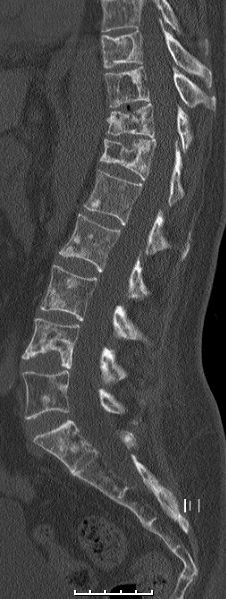

52-jährige Frau mit exulzeriertem, blutendem

Mammakarzinom T4b N3a M1. Diffuse Metastasierung der Wirbelsäule.![]() |